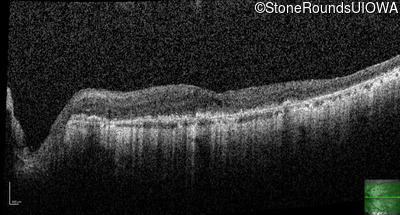

This 81 year old man began using a flashlight to read menus in his 40's. At age 75 his ophthalmologist noticed abnormal fundus findings and referred him to a retina specialist.

| Age at visit: 81 years |

| Age at visit: 82 years |

| Age at visit: 83 years |

| Age at visit: 84 years |

| Age at visit: 85+ (Visit 1) |

| Age at visit: 85+ (Visit 2) |